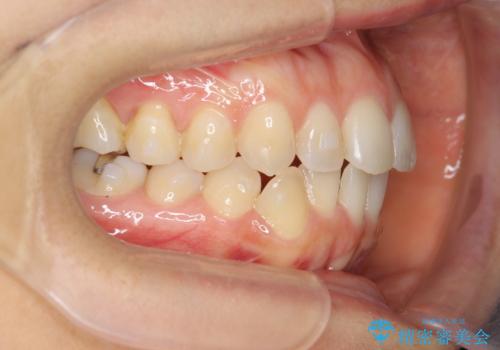

前歯のガタつきをマウスピースで治したい!

- 気になる前歯のガタつきをマウスピースで治療したいと希望され来院されました。

当日に矯正検査を行い、骨格・歯に問題がないことを確認しマウスピースによる矯正治療を進めます。

IPRを前歯部に少量行うことで、非抜歯でも前歯が外に飛び出さない仕上がりを達成できました。